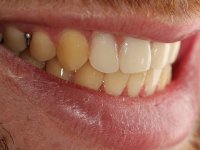

O paciente foi observado conjuntamente e a dúvida que surgiu de imediato foi se seria possível com a regeneração óssea a efectuar poder ser reabilitada naturalmente a zona das papilas interdentárias. Nesse sentido foi feito um enceramento de diagnóstico que contemplaria as duas hipóteses, utilizando ou não a cerâmica gengival. A confecção desse enceramento foi fundamental para expor ao paciente a dificuldade da reabilitação. O wax-up deu origem a um mock-up que foi aprovado pelo paciente e que simultaneamente serviu de guia imagiológica. O caso foi planificado cirurgicamente e realizada uma guia cirúrgica com que foram colocados os implantes. Após 10 semanas foi feita a 1ª impressão para confecção da ponte provisória. Foram criados os primeiros perfis de emergência na gengiva artificial e foi digitalizado o modelo. Por processo de CAD-CAM foi confeccionada uma ponte provisória aparafusada baseada no enceramento de diagnóstico. A ponte trabalhou durante 8 semanas os tecidos moles que foram fielmente copiados numa impressão com técnica de moldeira aberta. Os transferes foram individualizados com resina composta para copiarem fielmente os perfis de emergência criados pela ponte provisória. Confeccionado o modelo de trabalho definitivo, foi realizada uma infra-estrutura em zircónio seguindo a orientação do enceramento de diagnóstico. O assentamento da infra-estrutura foi testado em boca e simultaneamente foi novamente impressionados os tecidos moles com um silicone fluido. Nessa consulta foi feito o levantamento da cor. Os dentes 13 e 23 apresentavam uma saturação anormalmente forte que resolvemos não valorizar, optando por privilegiar a relação com o sector antero-inferior. Foi realizada uma nova gengiva artificial com a impressão que acompanhou a impressão de arrasto com a infra-estrutura. Após a colocação da cerâmica na infra-estrutura foram coladas as meso-estruturas. O trabalho final foi aparafusado lentamente permitindo a adaptação dos tecidos moles.